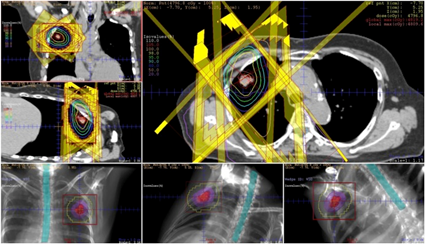

放射線治療計画CT

放射線治療の準備として、まず治療計画を立てるためのCTを撮影します。得られたCT画像から放射線治療医師が、病変や周囲正常組織の位置関係を三次元的に正確に同定し、放射線の投与量と照射範囲を厳密に設定することにより、正常組織の影響を最小限に抑え、かつ病変に集中的に放射線を投与できるように照射方法を決定します。

IGRT

IGRTとは、照射の直前や照射中にX線写真やCT画像を取得して、治療計画時の画像と重ね合わせて、骨やマーカーなどをもとに正確に合わせ込みを行い、位置のずれの量を求めて寝台位置の修正を行ってから照射を行います。

SRT(Stereotactic Radiotherapy:定位放射線治療)とは、局所的に多方向から放射線を投与する照射です。1回の照射で目的とする病変へ多くの線量を限局して与えることができるので、数回の照射で病変への放射線の効果を高めるとともに、治療計画時の画像との重ね合わせを行い、高精度な照射位置の再現をしてから放射線を照射します。

IMRTとは、コンピュータによる治療計画の最適化を行い、正常組織に投与されてしまう放射線の量を従来の外部照射よりも抑えることができ、かつ病変に集中的に放射線を投与することを可能にする照射です。当院では2011年よりIMRTを施行しており、主に前立腺がん、頭頚部がんに多く行っています。